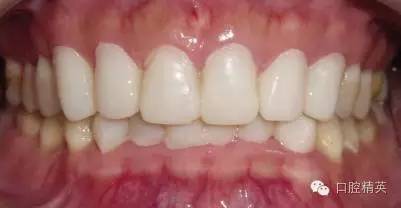

粘固后,對咬合關(guān)系進(jìn)行初步調(diào)整。三天后,復(fù)查,進(jìn)一步確認(rèn)咬合關(guān)系,必要時(shí)進(jìn)行調(diào)整(見圖12)。

LAVA 全瓷冠強(qiáng)度高,顏色自然,邊緣高度密合,切端可見半透明感,整體效果理想,與修復(fù)前(見圖1)相比取得了醫(yī)患均滿意的效果。